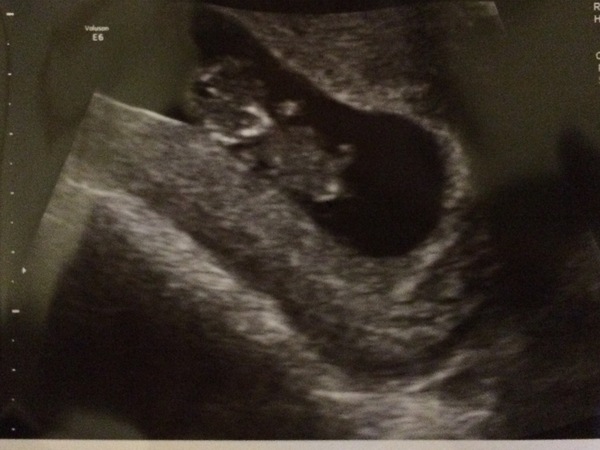

Kirstyinnorway · 27/01/2017 19:42

Here he/she is!

Just back from the most magic scan! Grin

Bean was waving, kicking and wiggling 😍 HB was good (120) I'm in love with my little blob! I measured a bit big at 10+2 (although I suspect that will change as I know when I ovulated)!

Home now with crisps and alcohol-free wine to celebrate... Today was a good day Smile

Yay Kirsty - wonderful news and such a gorgeous photo! Grin